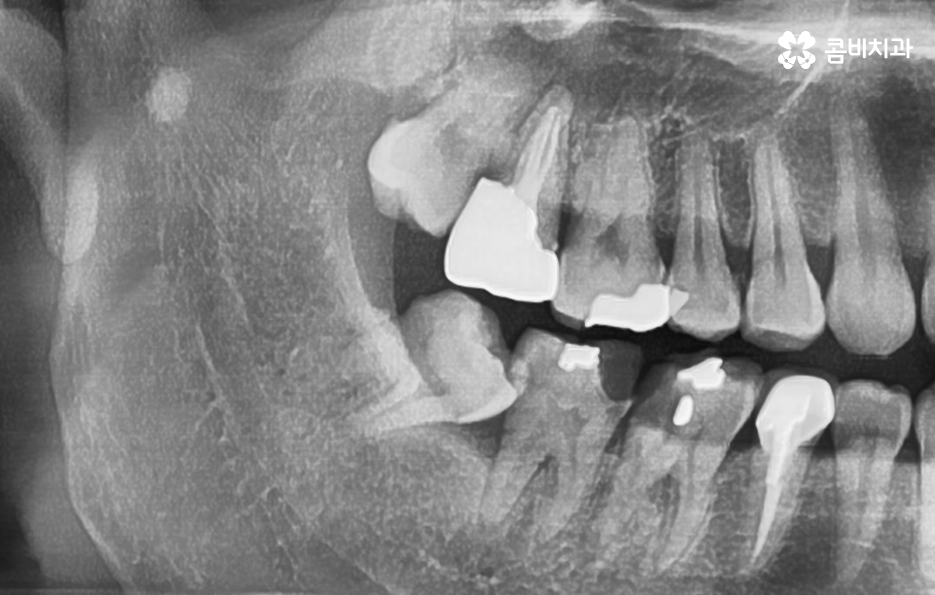

위 사례 이미지의 경우 그래도 다행인 점은 사랑니 발치 시점이 늦지 않아서 완전 누운 사랑니 임에도 큰 고생은 안했던 사례라고 본다면 아래 환자분의 사례는 이미 사랑니 뿐 아니라 어금니 까지 충치가 심해진 사례라고 할 수 있는데요

위 사례 이미지의 경우 사랑니가 누워 있는 정도는 덜하지만 사랑니 발치 시점이 늦어져서 사랑니와 인접 치아 모두 충치가 심해진 사례라고 할 수 있어요

사랑니 발치로 고생했던 분들의 사례를 살펴보면 발치 자체를 미루다가 사랑니 발치도 어려워지고 어금니도 함께 치료해야 하면서 치료비 뿐 아니라 자연치아의 손상이 커지는 경우가 대표적이며 사랑니로 인한 문제는 충치 뿐 아니라 사랑니와 어금니 사이 치조골이 녹아 내리면서 치주염이 심각해지는 경우도 많기 때문에 잇몸 건강에 대한 부분도 고려하실 필요가 있어요